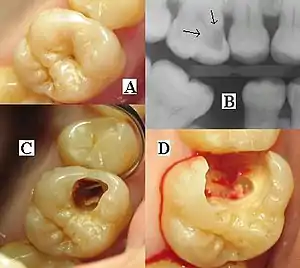

| Destruction of a tooth by dental caries and disease | |

The presentation of caries is highly variable. However, the risk factors and stages of development are similar. Initially, it may appear as a small chalky area (smooth surface caries), which may eventually develop into a large cavitation. Sometimes caries may be directly visible. However other methods of detection such as X-rays are used for less visible areas of teeth and to judge the extent of destruction. Lasers for detecting caries allow detection without ionizing radiation and are now used for detection of interproximal decay (between the teeth).

Primary diagnosis involves inspection of all visible tooth surfaces using a good light source, dental mirror and explorer. Dental radiographs (X-rays) may show dental caries before it is otherwise visible, in particular caries between the teeth. Large areas of dental caries are often apparent to the naked eye, but smaller lesions can be difficult to identify. Visual and tactile inspection along with radiographs are employed frequently among dentists, in particular to diagnose pit and fissure caries.[88] Early, uncavitated caries is often diagnosed by blowing air across the suspect surface, which removes moisture and changes the optical properties of the unmineralized enamel.